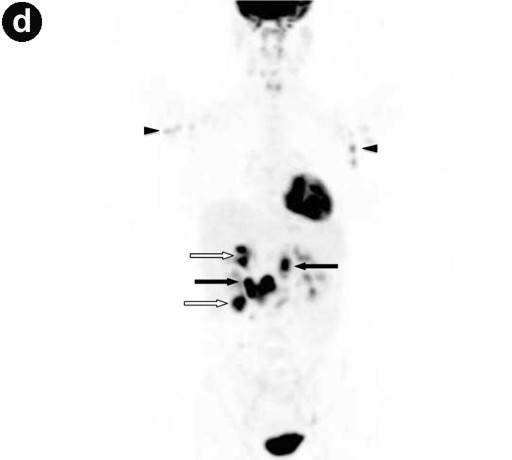

Contrast-enhanced MRI and diffusion-weighted imaging showed: a) an enlarged pancreas associated with highly restricted diffusion and delayed enhancement of the pancreas parenchyma as well as capsule-like peripheral enhancement in the late venous phase; b) main pancreatic duct strictures and chronic pancreatitis changes, suggesting possible autoimmune pancreatitis or a diffuse inflammatory process (Figure 1abc). Multiple mesenteric lymph nodes and two right renal mass-like lesions were also evidenced. 18F-fluorodeoxyglucose positron emission tomography/computed tomography (FDG-PET/CT) showed hypermetabolic activity within all lesions seen on MRI as well as less intense hyperactivity at the level of enlarged bilateral axillary lymph nodes (Figure 1d). These findings raised the hypothesis of lymphoma or tuberculosis. Endoscopic ultrasonography found a diffuse enlarged pancreatic gland and a 40 mm right renal mass. Fine needle aspiration (FNA) was performed both in the pancreas and in the kidney. Cytology showed non-specific inflammatory cells (Figure 2). IgG4-immunostaining was negative, serum IgG4 level was normal and anti-nuclear antibody was negative. Ultrasound-guided percutaneous renal biopsy was inconclusive, revealing a normal renal parenchyma. Cultures (containing a medium specific for mycobacteria and fungus) on FNA and percutaneous renal biopsy specimens were negative.

Figures 1. a. Fusion of axial MRI T2-weighted spin-echo and diffusion-weighted images showing high-intensity focal lesions in the pancreatic head (white arrow) and in the right kidney (black arrow). b. Late venous phase of contrast-enhanced axial MRI T1-weighted gradient-echo image showing a diffusely enhanced and enlarged pancreas with a high intensity capsule-like rim (arrows). c. MRCP image revealing a long segmental stricture (arrow) as well as dilatation and side branch ectasia of the main pancreatic duct. d. FDG-PET/CT showing multiple localizations of intense abnormal radiotracer uptake corresponding to the superior and inferior pole of the right kidney (open arrows), the head and body of the pancreas (closed arrows), and the axillary regions (arrowheads). |